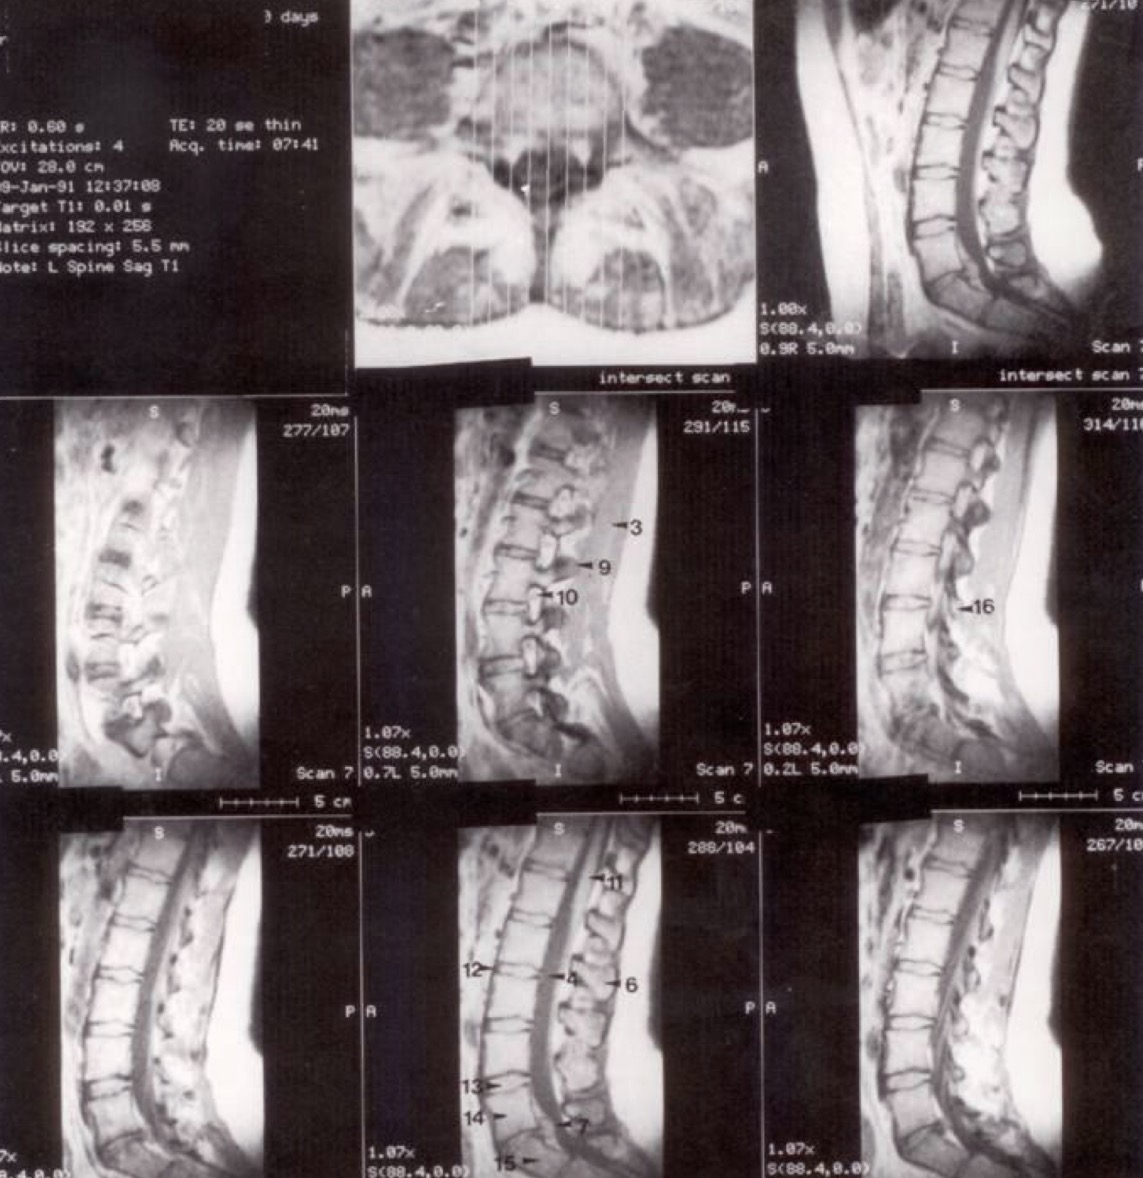

Metodika (a)

Horizontalūs (ašiniai) pjūviai per lumbosakralinę dalį. Pirmasis pjūvis yra žemiausias, kiti trys kyla į viršų per L IV - V diską.

Metodika (b)

Sagitaliniai (šoniniai) pjūviai. Vidurinis pjūvis matomas viršutinėje eilėje dešinėje, kiti seka eilės tvarka iš kairės į dešinę.

Klinikinis pastebėjimas

Mažas atstumas tarp stuburo ir priekinės pilvo sienos rodo, kad pacientas yra jaunas ir lieknas (mažai visceralinių riebalų).